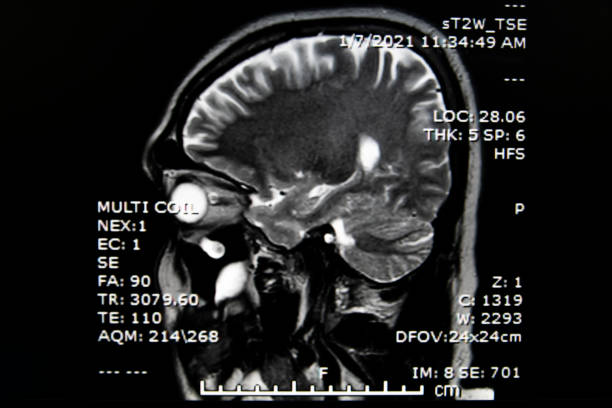

1. 전두엽 손상

뇌경색 후, 이마 부위에 손상이 생기면 하체의 힘이 약해질 수 있습니다. 이로 인해 환자는 걷거나 움직일 때 한 쪽으로 기울거나 반쪽의 마비가 발생할 수 있습니다. 대소변의 장애, 성격 변화, 사고력 저하, 집중력 감소 등과 같은 부작용도 나타날 수 있습니다.